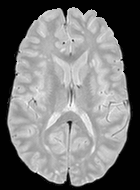

Patch size is another important parameter of the network. In computer vision applications such as object detection, usually a whole 2D image is used as a feature. However, full 3D medical images can not typically be used because of memory limitations. Fig. 4 shows examples of lesion memberships obtained with different sized 2D patches. As the patch sizes increases, the false positives that are mostly observed in the cortex tend to decrease. Fig. 5 shows a plot of Dice and LFPR with various patch sizes, ordered from left to right according to their increasing size. Note that smaller patches ( to ) produced significantly lower Dice and higher LFPR compared to other patches (), as seen from the memberships in Fig. 4. Also some of the highest Dice and lowest LFPR were observed for patches with large in-plane size, i.e., , , and . It was observed in Fig. 5 that there is no significant difference between Dice coefficients for , , or , but LFPR of both and are significantly lower than that of (). We chose as the optimal patch size. Other choices of smaller and patches (not shown) yielded worse results. Note that although training was performed with different patch sizes, the memberships were generated slice by slice, as the trained model consisted only of convolutions and did not need any information about patch sizes.

In our experiments, we used large 2D patches similar to Ghafoorian et al. (2017b), in comparison to isotropic 3D patches as used before, e.g., in Valverde et al. (2017), in Wachinger et al. (2017), and in Kamnitsas et al. (2017). The rationale behind using large anisotropic patches is twofold. First, experiments with full 3D isotropic or patches showed little or no improvement in Dice and led to increased false positives, with memberships similar to the one with patches, as shown in Fig. 4. Larger isotropic patches, e.g. or , showed inferior segmentation, and in some cases, optimization did not converge. The reason is that the FLAIR images in the test datasets had inherently low resolution in the inferior-superior direction, mm and mm compared to in-plane resolution of mm. Therefore 2D axial patches capture the high resolution in-plane information that represents the original thick axial slices. Second, the lesions are usually focal and small in size, unlike other brain structures. Therefore a very large isotropic patch around a small lesion can include superfluous information about the lesion, which can increase the amount of false positives. Note that with in more recent studies employing high resolution 3D FLAIR sequences, it is trivial to extend the algorithm to accommodate for 3D patches.